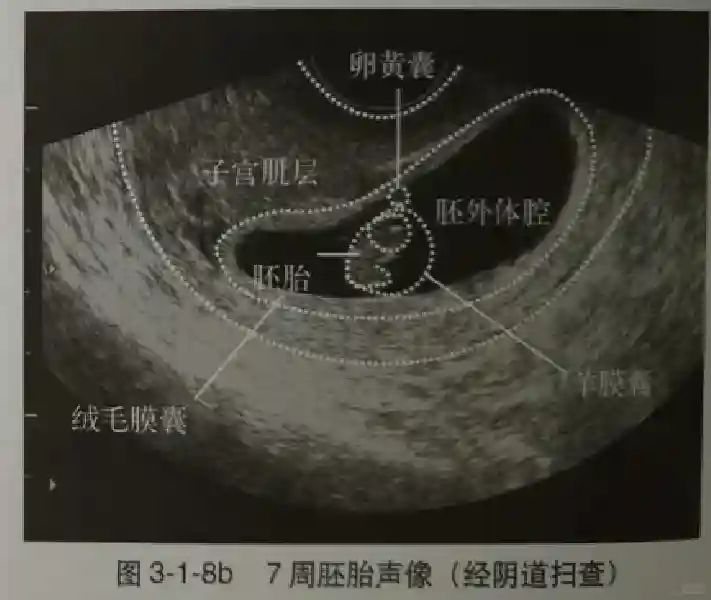

2️⃣卵黄囊:是妊娠囊内第一个解剖结构,直径<7mm。表现为小环状,中央为无回声,囊壁薄,内透声好。卵黄囊位于胚胎旁胚外体腔内。卵黄囊通常在孕5-6周时出现,5-10周稳步增长,一般不超过7mm,至12周消失。妊娠囊的大小与卵黄囊之间有一定关系,妊娠囊平均直径> 8 mm 时,经阴道超声均应显示卵黄囊,妊娠囊平均直径> 18 mm 时,经腹超声均应显示卵黄囊。

3️⃣胚胎:胚胎通常在6-7周时可以为超声显示,起初为胎芽,表现为卵黄囊一侧局部组织增厚,达到1 -2 mm 时才有可能为超声测量出来。达4-5mm时可见胎心搏动,相应孕周为6-6.5周,妊娠囊大小为13-18mm。胚芽长度≥7㎜时仍未见心管搏动,提示胚胎停止发育。胚胎的出现和妊娠囊直径的关系:妊娠囊直径> 16 mm 时,经阴道超声应显示胚胎。妊娠囊直径> 25 mm 时,经腹超声均应显示胚胎。

5️⃣羊膜:早孕期羊膜囊菲薄,超声常不能显示。孕7周以后加大增益或者用高频超声可以显示羊膜。羊膜囊位于绒毛膜内,胚胎位于羊膜囊内。随着胚胎增长,羊水增多,羊膜囊增大,孕12-16周时,羊膜与绒毛膜全部融合,胚外体腔消失。宫腔线一侧内膜内一圆形增强回声区,中央有小囊状液性暗区,宫腔线局部突起变形,称蜕膜内征,用于判断早早孕。#超声 #早孕检查 #妊娠